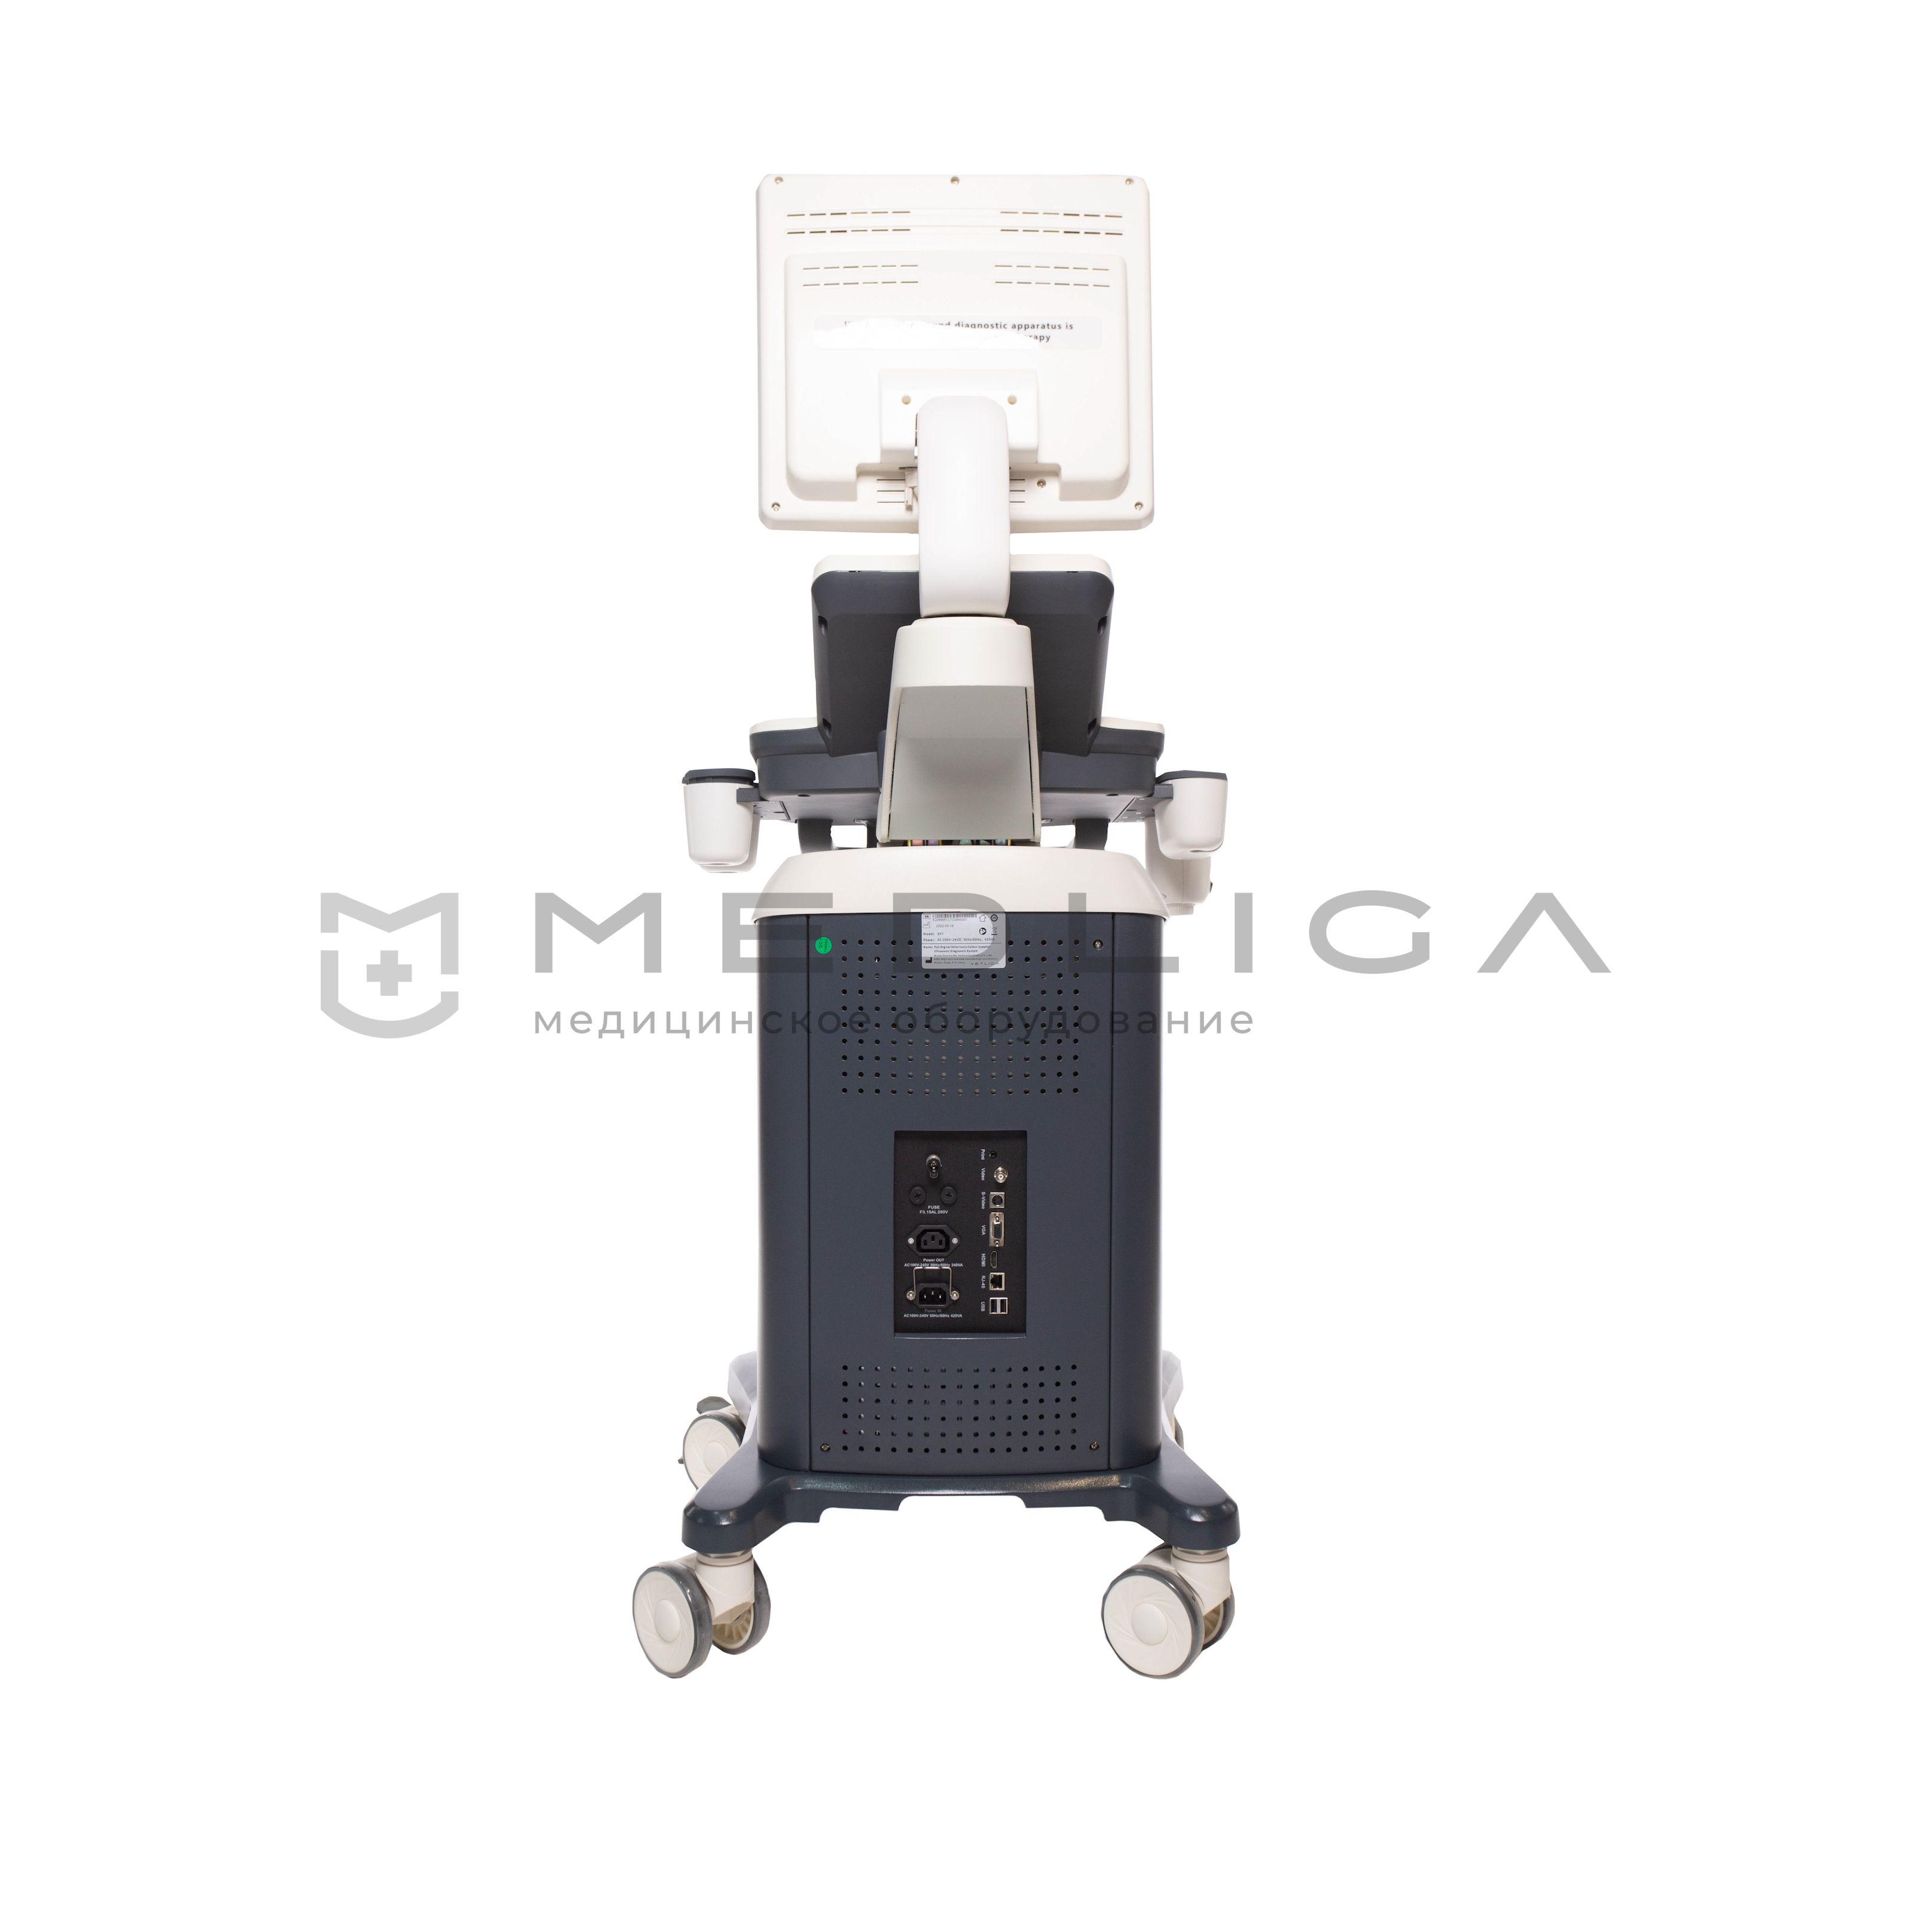

Ветеринарный УЗИ-сканер VETLIGA SP7

VETLIGA SP7 – ветеринарный ультразвуковой аппарат, работающий на новейшей технологической платформе uSeed. Прибор отличается эффективной обработкой и визуализацией изображений экспертного уровня, высокой производительностью и пропускной способностью.

VETLIGA SP7 - ветеринарный ультразвуковой аппарат, работающий на новейшей технологической платформе uSeed. Прибор отличается эффективной обработкой и визуализацией изображений экспертного уровня, высокой производительностью и пропускной способностью за счет предустановленных автоматических программ для исследования животных. 4 активных порта дают возможность подключать необходимые датчики и проводить весь спектр диагностических мероприятий.

Портативные сканеры легкие (5-15 кг) и компактные (размером с ноутбук), активно применяются в ситуациях, требующих скорой медицинской помощи, как на выездах, так и внутри лечебного учреждения. В больнице переносные приборы часто устанавливаются на специальную тележку, оснащенную держателями датчиков и другими опциями.

Стационарные аппараты также называют передвижными. Работают от электросети. Обеспечивают высокую производительность, обеспечивают точную диагностику, имеют дисплей с большей диагональю и наиболее удобную панель управления. Также могут иметь встроенную аккумуляторную батарею.